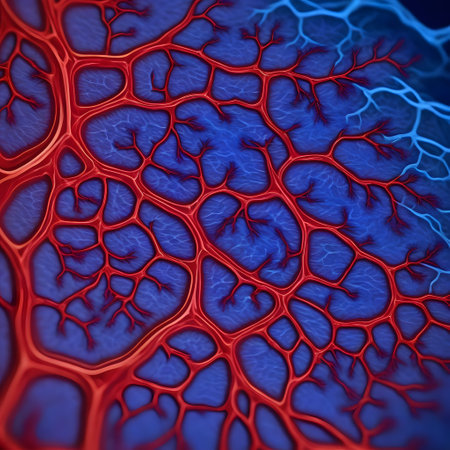

Macro view of human blood vessel network with red and blue tones showing capillaries and vein structure, ideal for illustrating medical anatomy and biology research.

Vessel flow texture in red and blue lighting showing microscopic circulation system pattern symbolizing human biology, anatomy, and healthcare science visualization.

Detailed visualization of intertwined red capillaries resembling a biological network, set against a dark blue backdrop